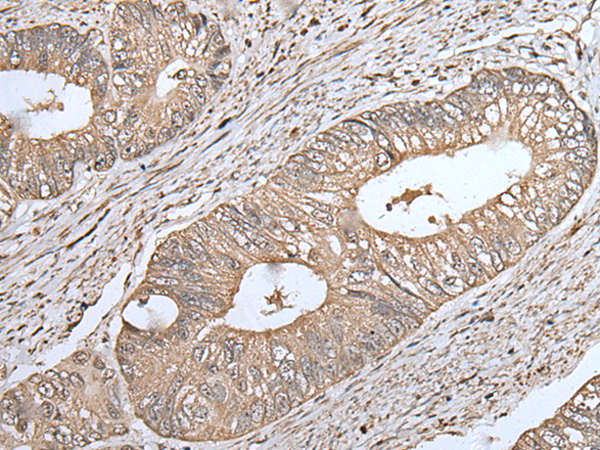

IHC positive control:

Human liver cancer

IHC Recommend dilution:

40-200